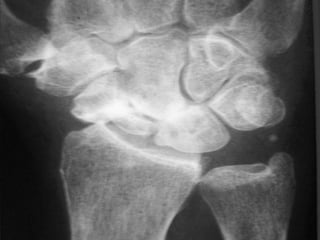

Radiography

 The 4 essential views (ie, PA, lateral, supinated and

pronated obliques) identify majority of fractures.

 The scaphoid view is a PA radiograph with the wrist

extended 30° and deviated ulnarly 20°. This view

helps to stretch out the scaphoid and is also used for

assessing the degree of scaphoid fracture angulation.

 A clenched-fist radiograph has also been useful for

visualization of the scaphoid waist.

Radiography  The 4essential views (ie, PA, lateral, supinated and pronated obliques) identify majority of fractures.  The scaphoid view is a PA radiograph with the wrist extended 30° and deviated ulnarly 20°. This view helps to stretch out the scaphoid and is also used for assessing the degree of scaphoid fracture angulation.  A clenched-fist radiograph has also been useful for visualization of the scaphoid waist.